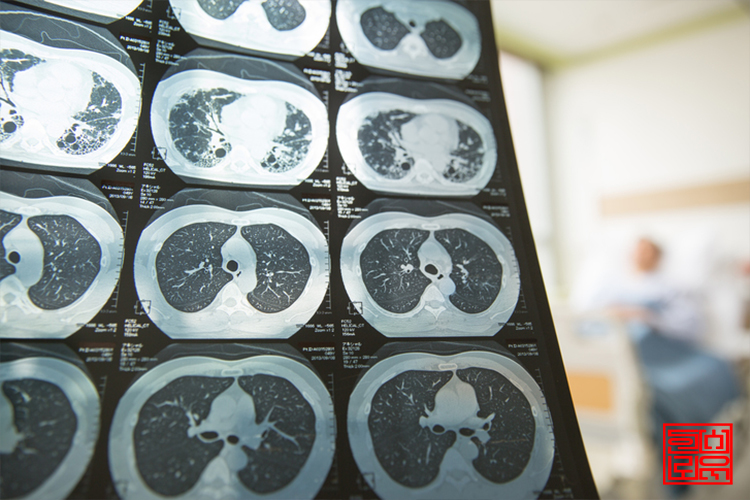

Á¦ÀÚ¸®¾Ï ¹× °æ°è¼ºÁ¾¾ç µî¿¡ ´ëÇÑ ¾Ï Áø´Ü±Ý û±¸